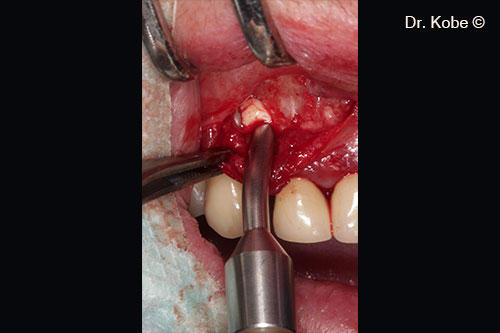

Root scaling and debridement

Root surface cleaned